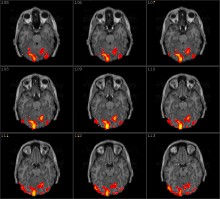

篇科学论文中,而且这个数字至今还在以每周30至40篇的速度增长。人们之所以对它如此重视,那是因为比起现有其他大脑功能成像技术,fMRI在“观察活动中的大脑”时,不仅时间分辨率更高,就连空间分辨率也可达到毫米水平。借助fMRI,对大脑的研究便可扩展至记忆、注意力、决定……在某些情况下,fMRI技术甚至能够识别研究对象所见到的图像或者阅读的词语。对个人内心世界的这些揭示不禁让人期待在大脑中鉴别谎言这种复杂状态的可能性。

人脑是人体最重要的器官之一,对于人脑功能的探求无疑是非常有意义的事情。长久以来,科学家们就注意到这样的事实: 即人脑的功能反映在大脑皮层是按空间分区的,在脑内次级结构也是按空间分隔的。研究脑功能映射(Function Brain Mapping)有许多成功的模式(Modality),例如正电子发射断层扫描(Positron Emission Tomography,PET),在向脑内注射15O水后,通过测量局部脑血流(rCBF)的方法来检测大脑的活动。脑电图(EEG)和脑磁图(MEG)也可检测大脑对诱发刺激响应的电或磁信号,但很难对活动区作准确的空间定位。也有人用光学的方法检测脑功能。例如近红外光谱仪和基于可见光的时间分解反射光谱仪,都是基于检测神经活动引起的脑血流和代谢改变。在众多的模式中,用于脑功能定位的磁共振成像(Magnetic Resonance Imaging,MRI)技术,或曰功能磁共振成像(Functional MRI)是一种非常有效的研究脑功能的非介入技术,已经成为最广泛使用的脑功能研究手段。最早起源于1991年春天,美国麻省总医院(Massachusetts General Hospital,MGH)的磁共振研究中心利用磁共振成像生成反映脑血流变化的图像。它虽然是一种非介入的技术,但却能对特定的大脑活动的皮层区域进行准确、可靠的定位,空间分辨率达到1mm,并且能以各种方式对物体反复进行扫描。

fMRI的另一个特点是,能实时跟踪信号的改变。例如在仅几秒钟内发生的思维活动,或认知实验中信号的变化。时间分辨率达到1s。大批的脑科学研究人员已经开始从事磁共振功能神经成像的研究,并将它应用于认知神经科学。医学领域的迫切需求也进一步促使fMRI技术的发展,一些在病理方面的应用已初见端倪,例如利用扩散(Diffusion)成像和灌注(Perfussion)成像技术对大脑局部缺血进行诊断等。本文着重介绍功能磁共振的原理及应用方面的现状和前景。